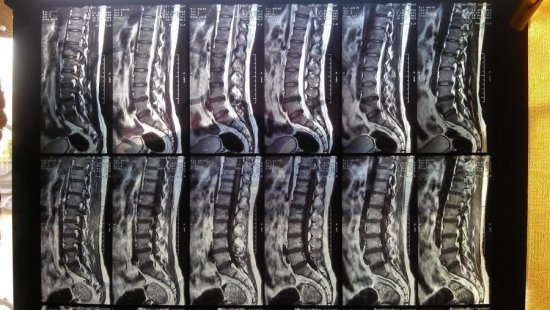

Боли в крестцовом отделе позвоночника свидетельствуют о патологических изменениях в опорно-двигательном аппарате. Сильные перегрузки спины, травматизация способствуют болевому синдрому в пояснично-крестцовом отделе позвоночника. Боль в крестцовом отделе позвоночника у женщин может появиться из-за патологий внутренних органов, такой болевой синдром является сигналом развития патологического процесса.

Если возникает болевой синдром поясничного отдела позвоночника, то часто причиной является остеохондроз. Пациента болит спина в области крестца, поясницы, болевые ощущения иррадиируют в нижние конечности. В спине человек почувствует перенапряжение, она будет скованной. Иногда чувствительность нарушается. Такое напряжение приведет к тому, что позвоночник потеряет гибкость, двигательная активность затруднится.

Болевые ощущения также возможны при грыжах между позвонками поясничного сегмента

Часто патологические изменения крестцового и копчикового сегмента при рентгенологическом исследовании не проявляются

Обращаются к доктору для последующей диагностики и лечебных мер. Важно помнить, перед тем, как проводить мануальные способы лечения на позвоночнике, мануальный терапевт обязан направить больного на компьютерную или магнитно-резонансную томографию. Если диагностирована межпозвоночная грыжа большого размера, то показана операция. Грыжа удаляется, нервные корешки восстановятся, боль пройдет.